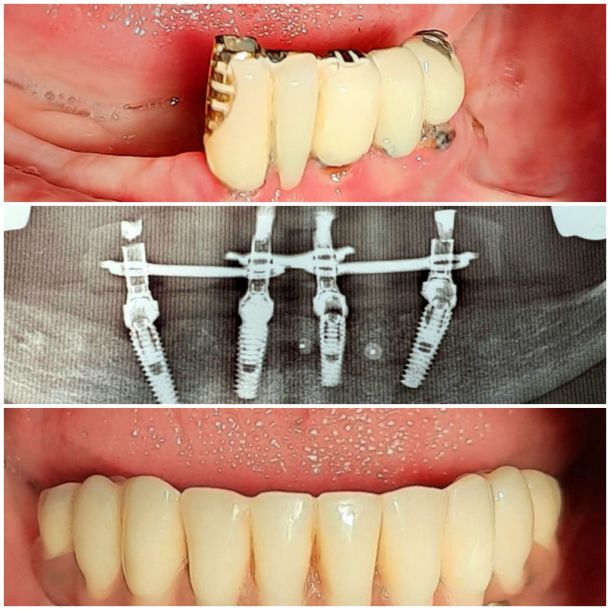

Фотогалерея клініки

Ваша посмішка

в надійних руках